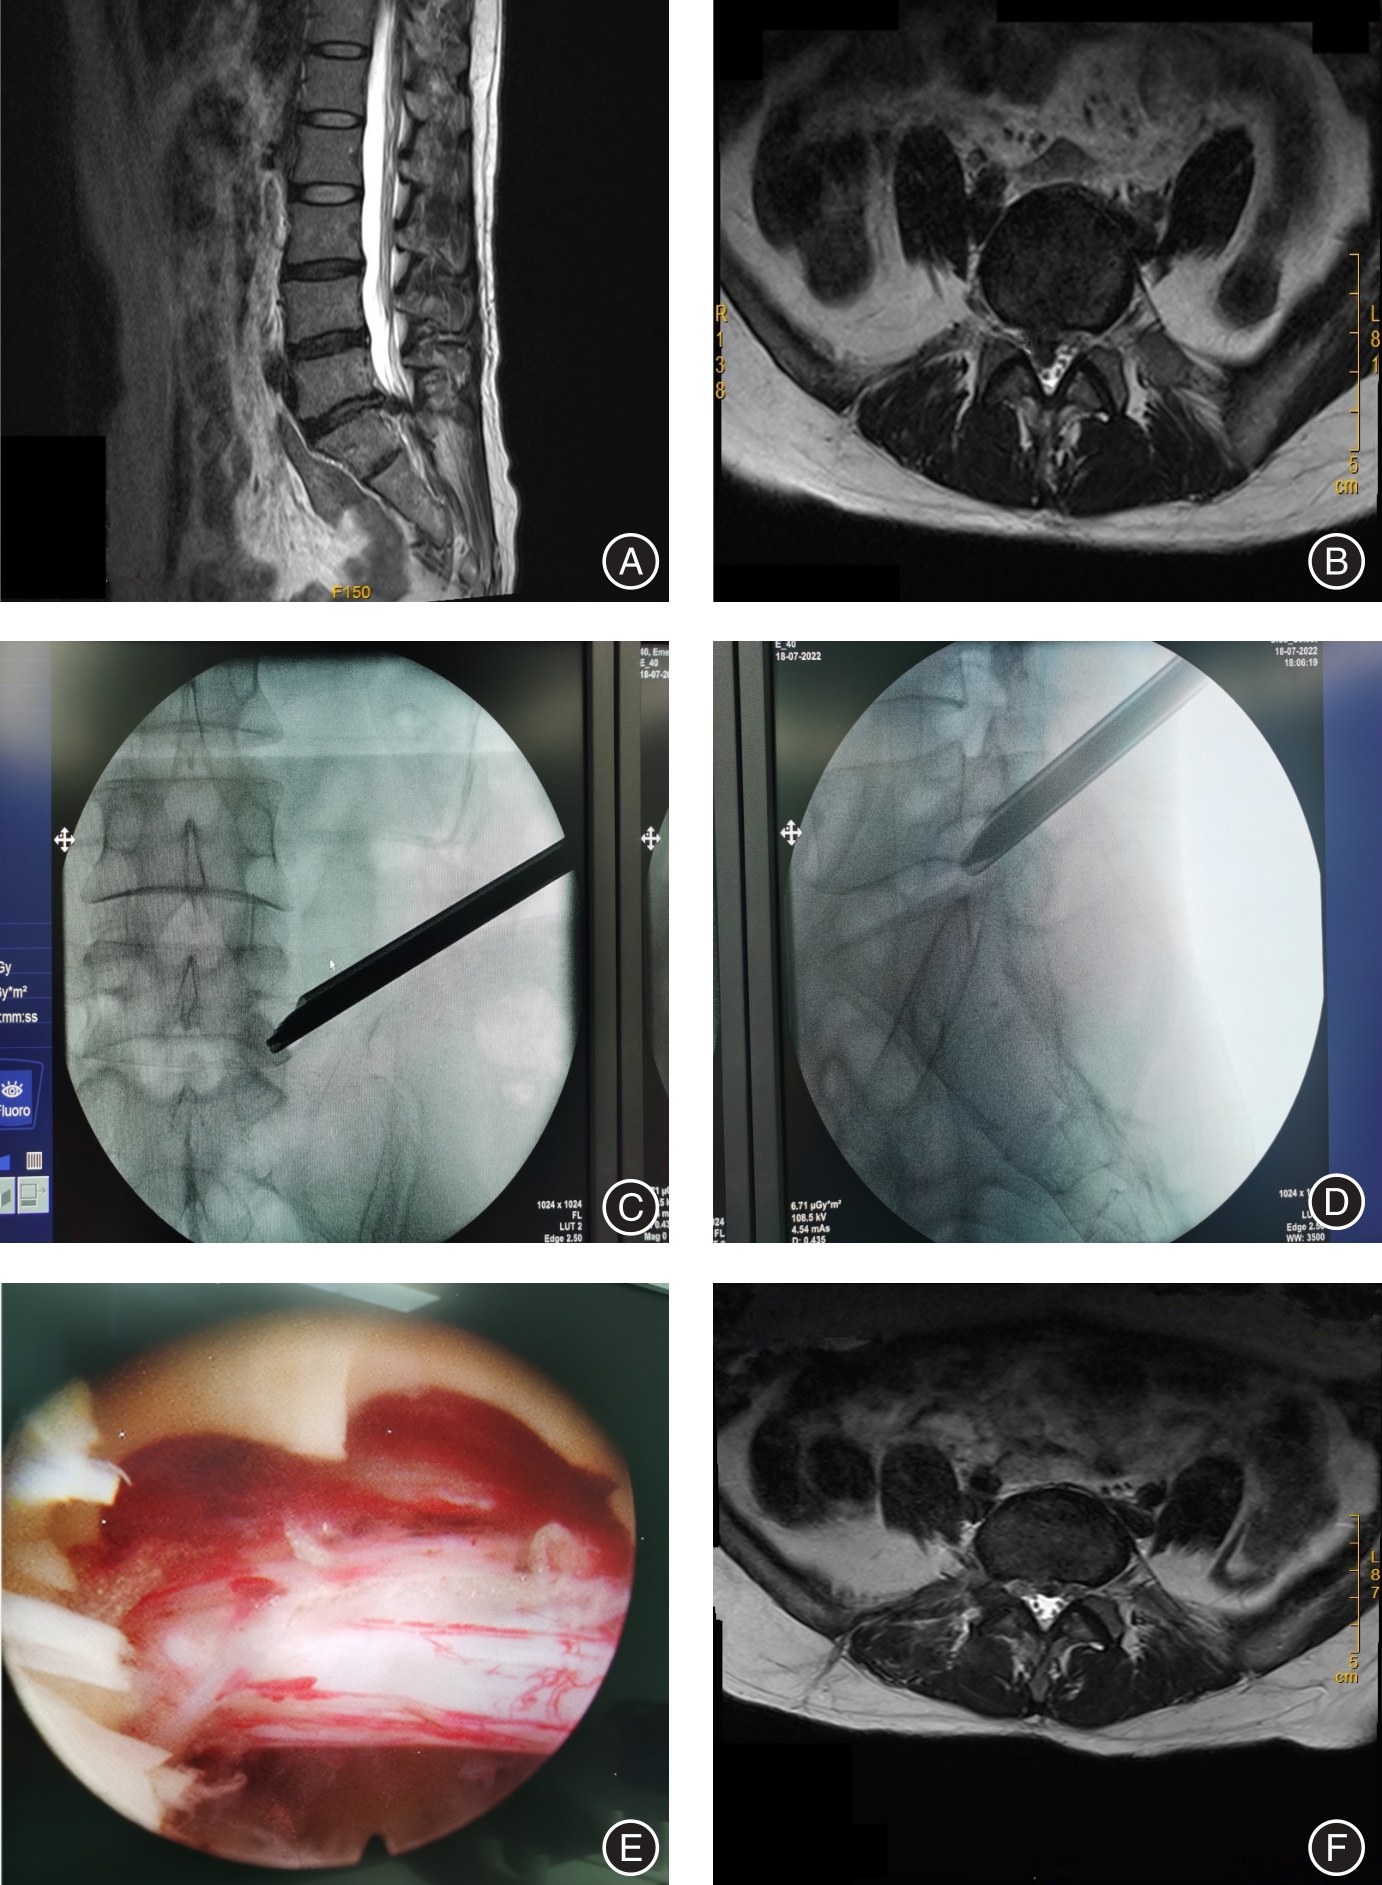

目的 分析经皮经椎间孔入路与经椎板间入路内窥镜下椎间盘切除治疗腰5/骶1椎(L5/S1)间盘突出症(LDH) 的疗效对比。 方法 采用回顾性病例对照研究,选取2020年6月至2022年12月在亳州医院脊柱外科采用经皮内窥镜手术治疗L5/S1 LDH患者62例,其中采用经椎间孔入路 32例(TELD组),采用椎板间入路 30例(IELD组)。观察指标包括术中透视次数、手术时间、住院时间、住院费用、腿痛VAS评分、ODI评分、改良MacNab疗效评价和并发症情况。 结果 62例患者均顺利完成手术和随访,无严重并发症发生。两组间在手术时间、透视次数和住院费用方面差异有统计学意义(P < 0.001),两组住院时间差异无统计学意义(P > 0.05),两组患者术后2 d、1个月及末次随访时下肢VAS评分较术前明显改善(P < 0.001)、两组患者术后2 d、1个月及末次随访时ODI评分较术前明显改善(P < 0.001),但两组间同时间点比较差异无统计学意义(P > 0.05);两组在手术优良率方面差异无统计学意义(P > 0.05),TELD组有高髂嵴患者11例均顺利完成手术。 结论 经椎间孔入路和经椎板间入路内镜手术治疗L5/S1LDH均能取得满意效果。但经椎间孔入路局部麻醉,住院费用少,伴有高髂嵴患者选择合适穿刺路径均可以顺利完成手术。经椎板间入路透视次数少,手术时间较短,但是出现硬脊膜及神经损伤风险较高,对于新手来说需要小心操作。

Objective To compare the efficacy of percutaneous transforaminal approach and translaminar approach in the treatment of L5/S1 disc herniation (LDH) under endoscopic discectomy. Methods Adopted a retrospective case-control study, and selected 62 cases of patients with L5/S1 LDH who were treated with percutaneous endoscopic surgery in the spine surgery department of our hospital from June 2020 to December 2022, and the transforaminal approach was used. (TELD) in 32 cases (TELD group), and interlaminar approach (IELD) in 30 cases (IELD group). The observation indicators included intraoperative fluoroscopy times, operation time, hospitalization days, hospitalization expenses, leg pain VAS score, ODI score, modified MacNab curative effect evaluation and complications. Results All 62 patients successfully completed the operation and follow-up, and no serious complications occurred. There were statistically significant differences in operation time, fluoroscopy times, and hospitalization expenses between the two groups (P < 0.001), but there was no significant difference in hospitalization days between the two groups (P > 0.05). The lower extremity VAS scores at the last follow-up and the last follow-up were significantly improved compared with those before operation (P < 0.001), and the ODI scores of the two groups were significantly improved at 2 days, 1 month and at the last follow-up (P < 0.001). At the same time point, there was no statistical difference (P > 0.05); there was no significant difference in the excellent and good rate of surgery between the two groups (P > 0.05). 11 patients with high iliac crest in the TELD group successfully completed the surgery. Conclusions Both the endoscopic surgery through the intervertebral foramen and the interlaminar approach can achieve satisfactory results in the treatment of L5/S1 LDH. However, local anesthesia through the intervertebral foramen approach reduces hospitalization costs, and patients with high iliac crest can successfully complete the surgery by selecting a suitable puncture path. The translaminar approach has fewer fluoroscopy times and shorter surgical time, but there is a higher risk of dura mater and nerve damage, which requires careful operation for beginners.